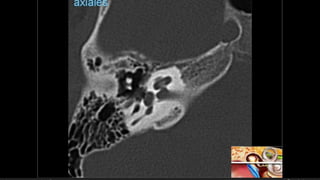

Hipoacusia

 Conductiva  26-57% -- longitudinal – lesión osicular, MT, Hemotimpano

 Sensorial  14-23% -- transversa -- OCV

 Mixta  20-55%

 Dislocacion incudoestapedial  57-80%

 Dislocacion incudomaleolar 51%

 Fractura estapedio  30%

Hipoacusia  Conductiva 26-57% -- longitudinal – lesión osicular, MT, Hemotimpano  Sensorial  14-23% -- transversa -- OCV  Mixta  20-55%  Dislocacion incudoestapedial  57-80%  Dislocacion incudomaleolar 51%  Fractura estapedio  30%  Fractura martillo  8%